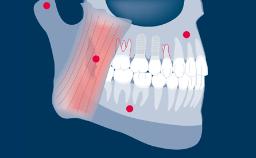

Transitional prostheses play an important role in replacing missing teeth during implant therapy, up to the point when the implants are ready to be restored.

Implant therapy often involves several clinical and laboratory stages, and transitional prostheses seek to ensure that the patient is comfortable on both an esthetic and a functional level throughout the duration of treatment.

Transitional prostheses also have important diagnostic functions, and they can be a key factor in achieving patient satisfaction with the definitive treatment outcome.

- list indications for transitional prostheses

- outline options for transitional prostheses

- describe advantages and disadvantages of fixed and removable transitional prostheses

- select an appropriate transitional prosthesis